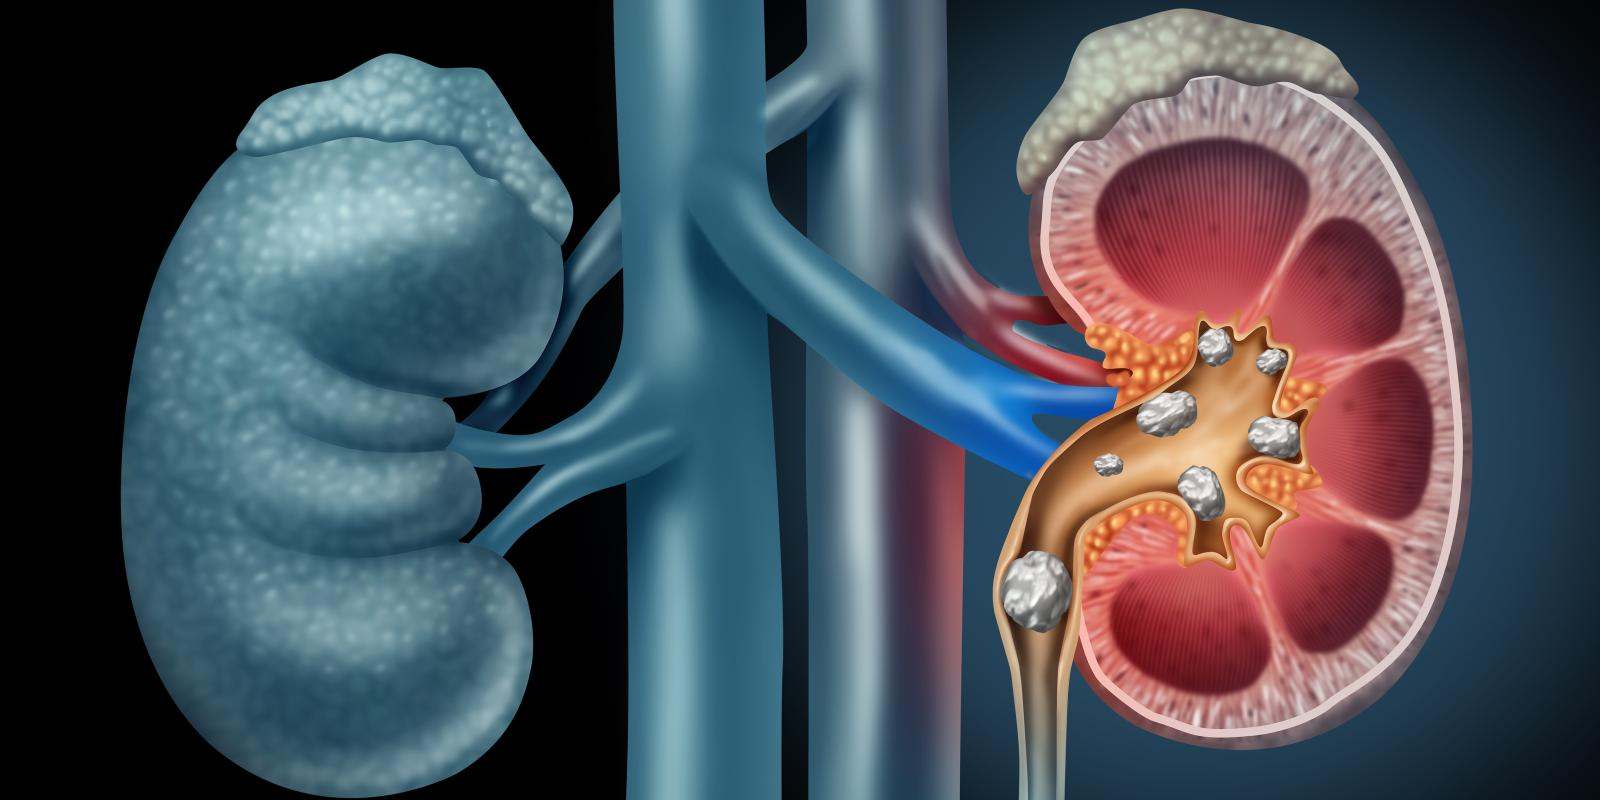

Todos podemos desarrollar cálculos o piedras en nuestros riñones. Su formación depende de varios factores que no siempre están en nuestra mano. De hecho, es tan frecuente esta afección que, según datos de la Sociedad Española de Nefrología, más del 10% de la población padecerá algún episodio somático de litiasis renal, como así se denomina a esta patología, antes de cumplir los 70 años.

“La litiasis es una enfermedad del riñón y de las vías urinarias donde la producción de orina no es la correcta. Con ello, se conforman agregados cristalinos dando lugar a un cálculo o piedra en el interior de la vía”, explica la doctora Pilar Bahílo, uróloga del Hospital Quirónsalud Valencia.

La uróloga del Hospital Quirónsalud Valencia señala que las piedras en el riñón suelen formarse cuando las sustancias que forman cristales (calcio, ácido úrico…) es mayor de la que pueden diluir los líquidos presentes en la orina, si bien precisa que a menudo los cálculos no tienen una causa definida. “La mayor parte de los cálculos se expulsan al orinar. No obstante, algunas veces se atascan en el uréter, bloquean el flujo normal de la orina y provocan molestias al paciente”, agrega.